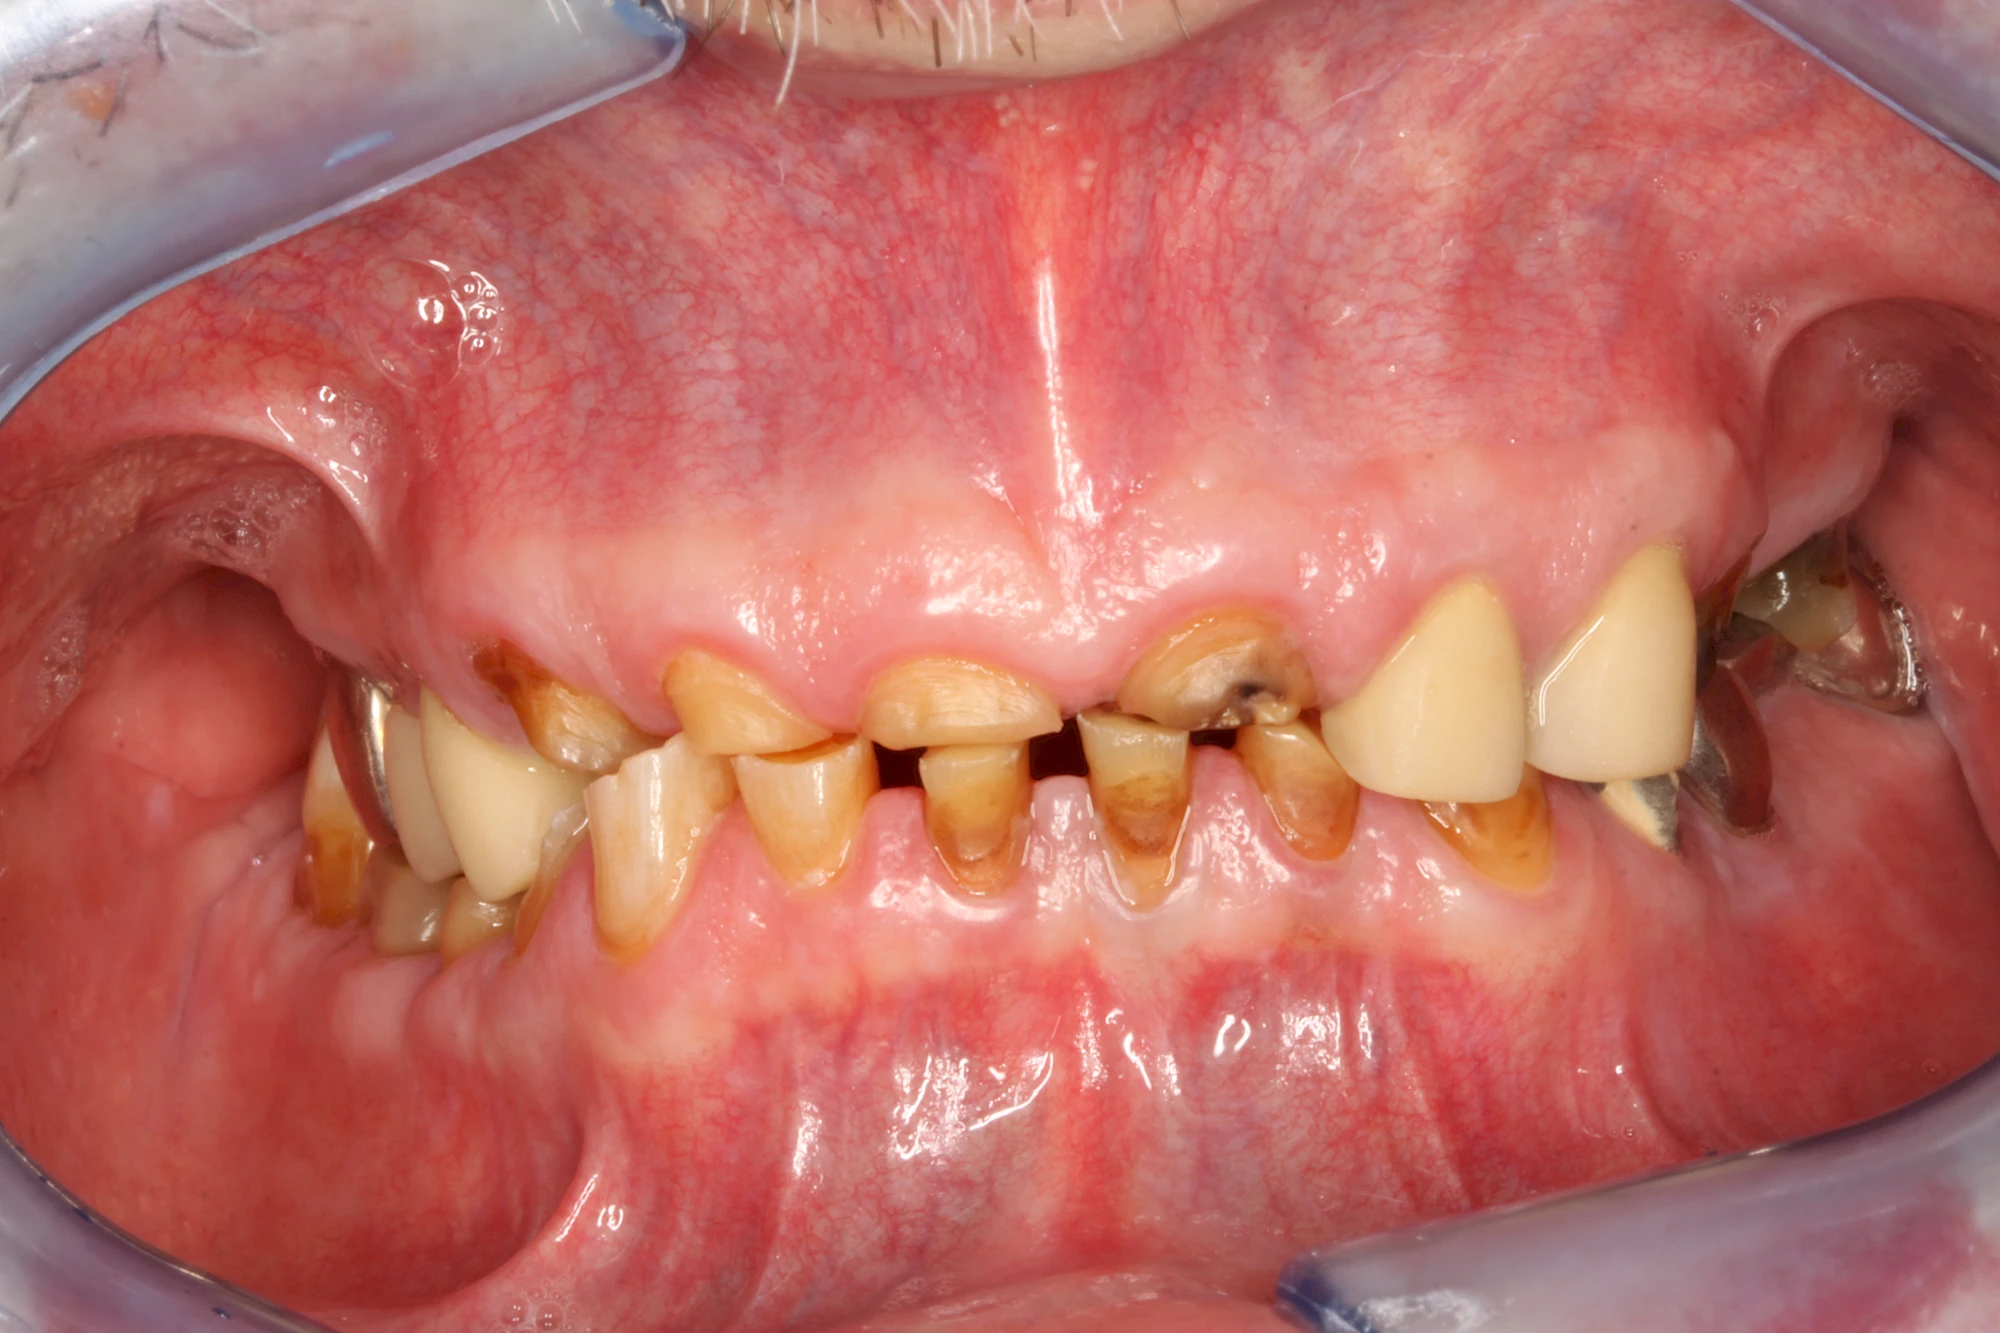

Über die Zeit können verschiedene Prozesse die Zahnhartsubstanzen aufzehren:

- Abnutzung durch Kauen (Abrasion) oder duch durch übermäßiges Knirschen bzw. Pressen (Attrition)

- Säurebedingte Auswaschung (Erosion)

- Knirschen bzw. Pressen und ungünstige Putztechnik (Druck): keilförmige Defekte

Auswaschung (Erosion) dagegen ist eine Verschleißerscheinung der Zähne aufgrund von immer wiederkehrenden Säureangriffen durch die Nahrung, verstärkt zum Beispiel durch den Genuss säurehaltiger Getränke oder Speisen. Auch bei Menschen mit einer Essstörung (z. B. Bulimie) können die Zähne durch die Magensäure ausgewaschen erscheinen.